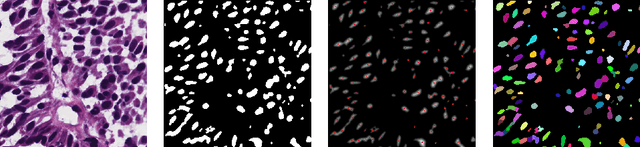

Abstract:Segmentation and accurate localization of nuclei in histopathological images is a very challenging problem, with most existing approaches adopting a supervised strategy. These methods usually rely on manual annotations that require a lot of time and effort from medical experts. In this study, we present a self-supervised approach for segmentation of nuclei for whole slide histopathology images. Our method works on the assumption that the size and texture of nuclei can determine the magnification at which a patch is extracted. We show that the identification of the magnification level for tiles can generate a preliminary self-supervision signal to locate nuclei. We further show that by appropriately constraining our model it is possible to retrieve meaningful segmentation maps as an auxiliary output to the primary magnification identification task. Our experiments show that with standard post-processing, our method can outperform other unsupervised nuclei segmentation approaches and report similar performance with supervised ones on the publicly available MoNuSeg dataset. Our code and models are available online to facilitate further research.